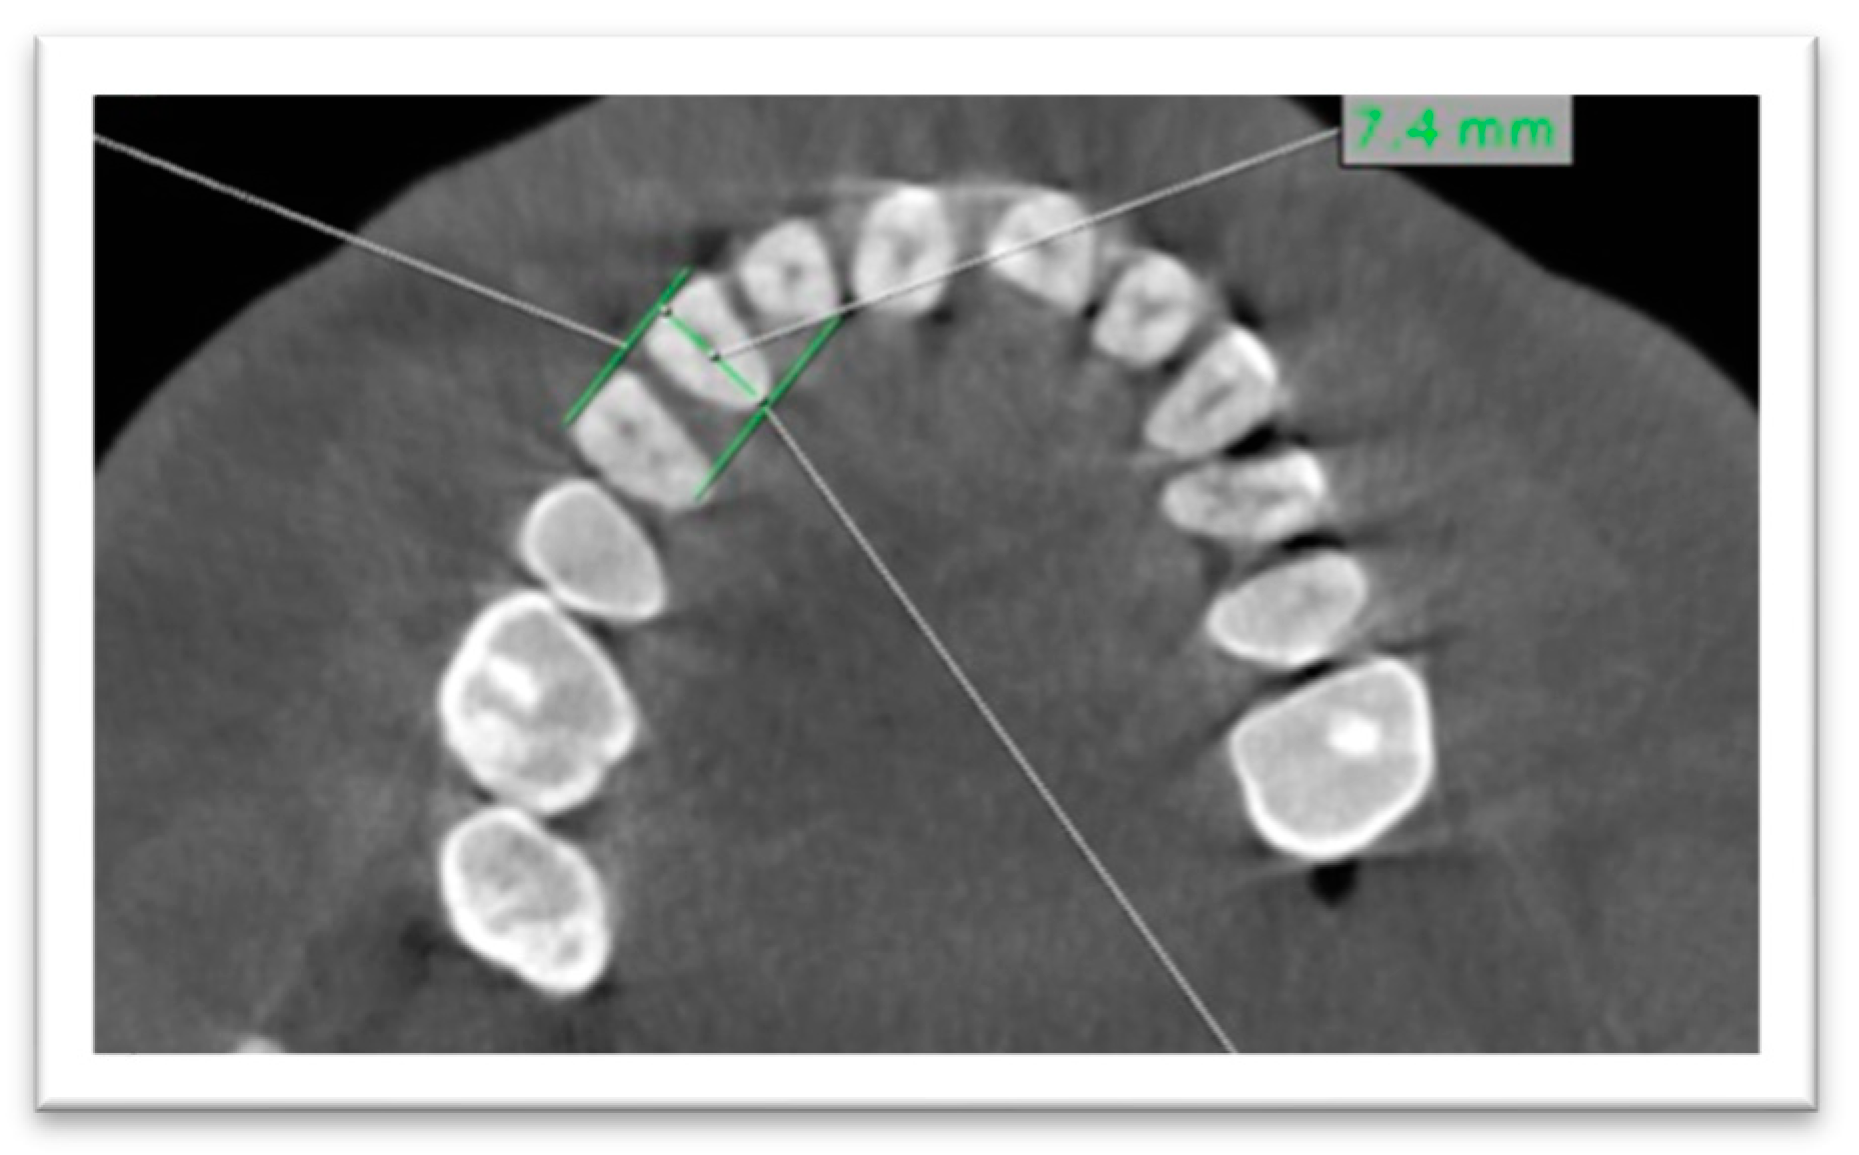

- (2)

- Regarding buccopalatal diameter, it was measured at the level of CEJ by a line bisecting the tooth on the axial plane (Figure 2).